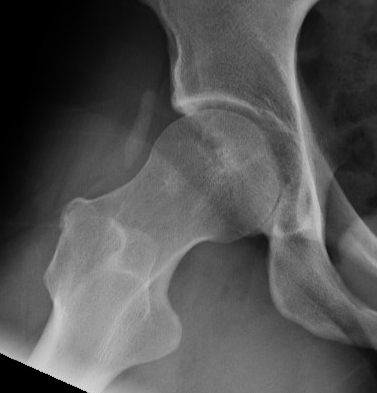

Anterior Cam

- hip flexed to 45 degrees

- image intensifer rotated 20 degrees posterior and 20 degrees distal to allow Dunn view

Anterior cam resection with hip flexed

Intra-operative Cam resection using Dunn view

Lateral Cam

- hip in extension / internal rotation

Lateral cam resection with hip in extension